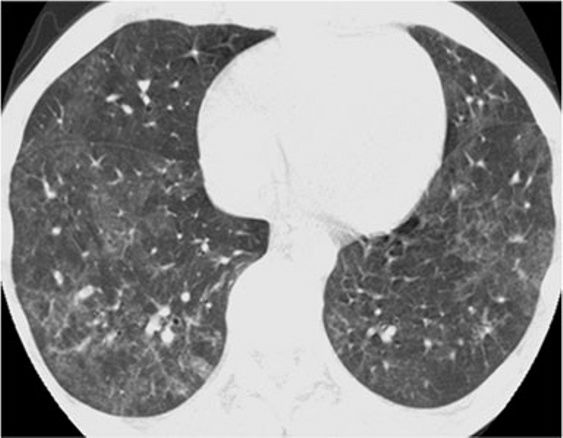

6、结节影

HRCT上的结节性形态的特征是存在许多圆形密度影,直径范围从2 mm到1 cm,微结节的直径小于3 mm [38]。除临床情况和辅助检查结果外,鉴别诊断主要基于解剖分布的三种不同模式:淋巴分布、随机分布和小叶分布。淋巴分布的特征是沿支气管周围血管间质,小叶间隔和胸膜下区域存在结节。随机分布显示结节,没有任何特定的站点优势。小叶小结节距胸膜表面,小叶间裂或小叶间隔几毫米。中心小叶分布进一步分为有和没有树芽状分布的结节。

6.1淋巴管分布结节

按淋巴管分布的结节典型疾病是结节病。结节主要位于肺门附近及中上肺野。

*结节病 上叶水平的HRCT表现为“无树芽征的结节状结节”,其特征是小叶间隔,裂隙,支气管血管束和胸膜周围存在淋巴小结节。

矽肺病的是结节病的模仿者,通常表现为淋巴管和小叶中心尖锐的微结节,范围从2mm到5 mm。结节的定义清晰且密度均匀,上叶和后段为主。支持矽肺病诊断的明显发现是微结节的聚结,淋巴结的蛋壳钙化形成的团块(罕见,仅占结节的5%)病例和胸膜下假性斑块的形成,同样是基于胸膜下微结节的合并。在大多数情况下,有接触史。

*矽肺病。上叶水平的CT表现为“无树芽征的结节状影”,特征是明确定义的均质小叶结节,主要位于上叶和后段。